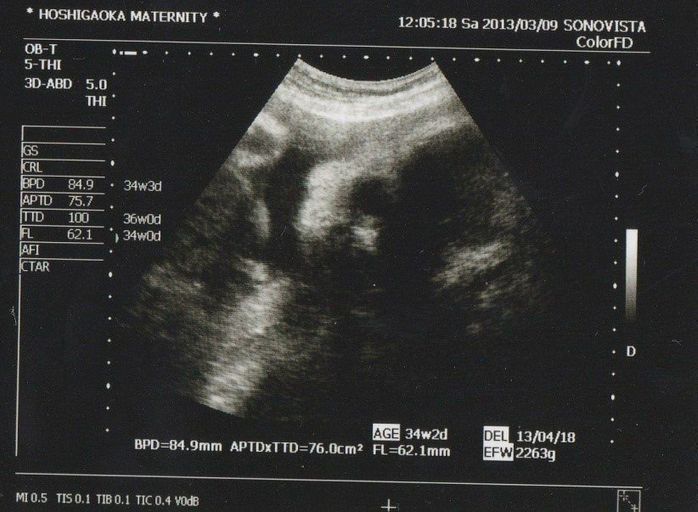

妊娠33週目のエコー写真

推定体重は2263gになりました。4週間前から760gも成長! こちらをじーっと見ている次女です。丸い黒いのが目で、三角の白い部分が鼻です。お姉ちゃんの声に敏感なのか、話しかけながらおなかをちょんちょんとすると、よく動きました。エコー写真だけでなく、胎動からも妹の存在を感じられた長女でした。